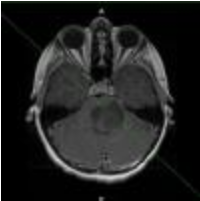

大脑扫描:磁共振成像(MRI)和计算机断层扫描(CT或CAT扫描),使用计算机创建大脑的详细图像,是较常见的扫描诊断脑肿瘤。

治疗后,可以进行脑部扫描(通常是MRI)以检查肿瘤生长。有时候,扫描显示看起来像是复发性肿瘤的区域,但是这通常是由放射治疗方法,化疗或两者引起的死亡组织或健康组织的变化。神经外科医生和神经放射学家将密切关注这一点,以确定胶质瘤是否复发。如果是这样,你的神经外科医生可能会介绍另外一个手术程序